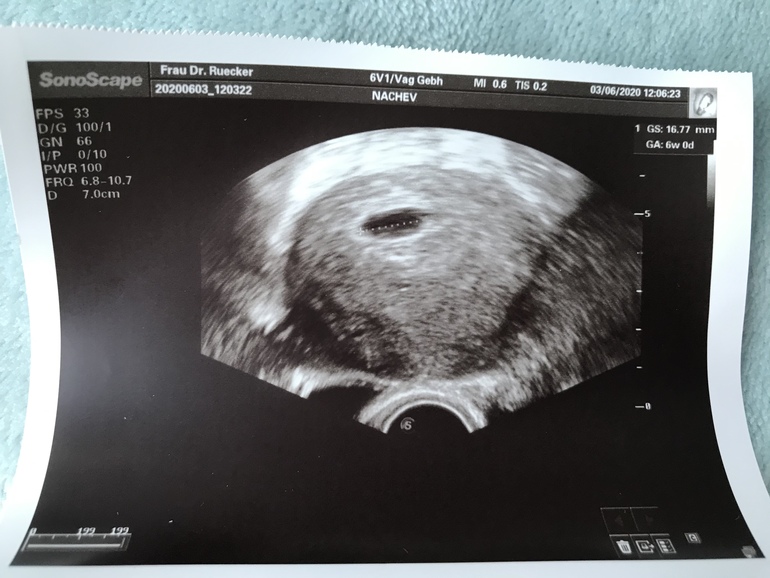

Беременность- 1 триместр ( только до 10 недель)Добрый вечер. Сегодня была у гинеколога , делали УЗИ . 6 недель(акушерских) , но плода не видно.. это нормально?

Врач сказала, что беременность есть (это и видно на фото), что все хорошо И она так же сказала, что из-за того, что маленький срок, плода просто ещё не видно. Просто, вышла от врача, залезла в интернет, начиталась разных статей не хороших и вот накрутила себя и переживаю.

Ваша врач права. Я тоже была в 5+5 только пя+ dottersack увидели (без эмбриона). Примерно в 6+4 можно будет уже увидеть сб. Не волнуйтесь 🍀